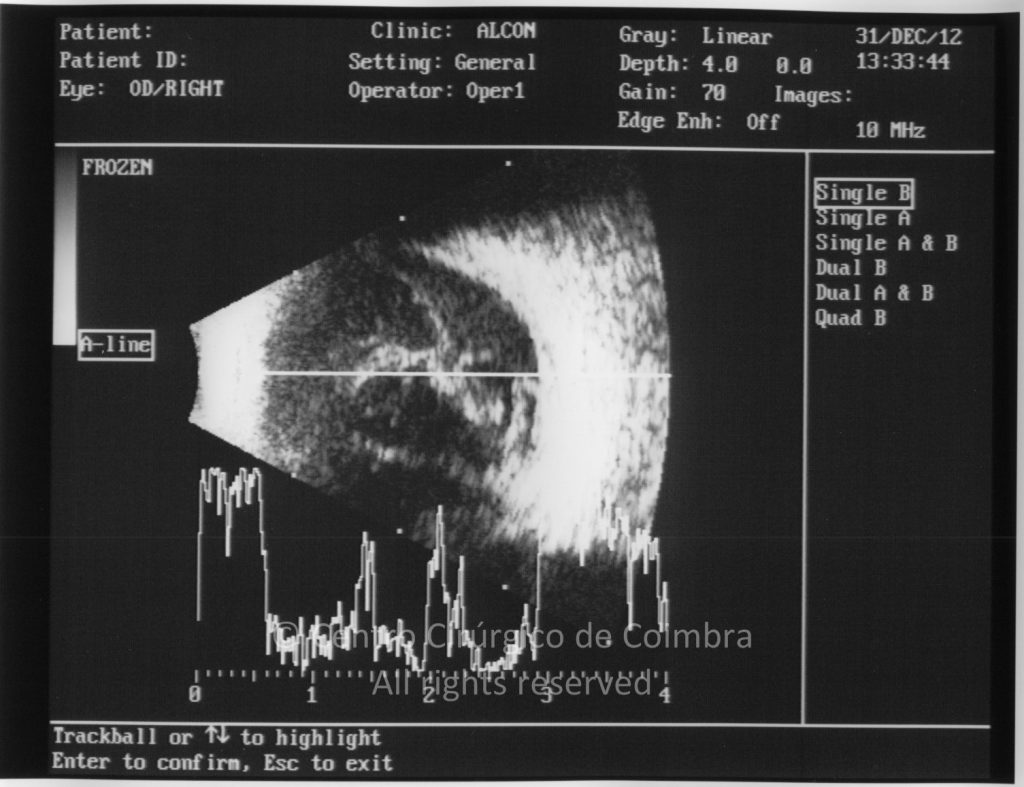

Paciente de 37 años con traumatismo contundente y ruptura del globo ocular. Presenta ruptura esclero-uveal, hifema, hemovítreo, desgarro periférico y temporal de la retina, hemorragias subretinianas y múltiples desprendimientos serosos.

MAVC: 20/25 OD, nueve años después de las cirugías (sutura escleral de la desinserción del músculo recto externo, vitrectomía posterior y fotocoagulación láser en el borde del desgarro retiniano, desprendimiento de retina inferior con proliferación vitreorretiniana y líquido subretiniano con algo de sangre; peeling de la membrana epirretiniana y maculorrexis de la MLI).